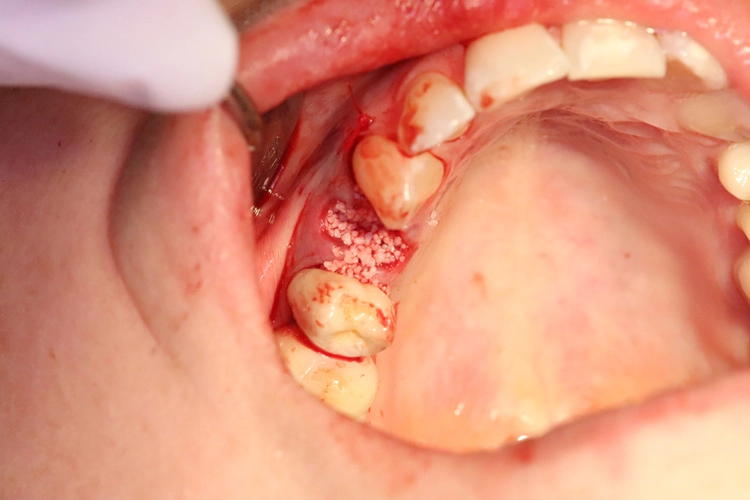

Aufgrund der traumatischen Extraktion des ankylosierten Zahnes, die zu einer Osteotomie wurde (Abb. 3), fehlten die vestibuläre und palatinale Lamelle (Röntgenkontrollbild während der Osteotomie, Wurzelrest noch vorhanden Abb. 4). Dieser Wurzelrest wurde entfernt. Bei dem geringen Restknochenvolumen war eine Sofortimplantation nicht mehr indiziert.

Der Erhalt der Weichgewebsstrukturen und des Kieferkamms wurde durch das Einbringen eines Knochenaufbaumaterials im Sinne einer Socket/Ridge Preservation ohne Membran gewährleistet (Abb. 5). Mesial zum 13 wurde eine resorbierbare Naht (SABAsorb rapid) gesetzt, um die Weichgewebe zu adaptieren. Die Kontrolle des Heilungsverlaufs nach dem Eingriff erfolgte ein Tag später (Abb. 6).